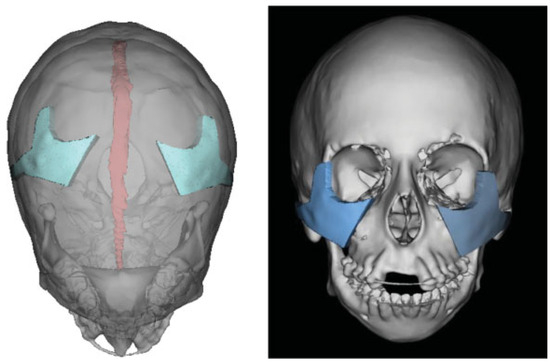

The patient underwent a complete preoperative orthodontic assessment prior to orthognathic surgery. Given the degree of lower facial asymmetry and the complexity anticipated with bimaxillary movements, we utilized VSP to design the operation. Standard cephalometrics were performed based on 3D CT (Table 1). Computer-aided simulation surgery was performed to first advance and rotate the mandible in the counter-clockwise direction to decrease the obtuse gonial angle, lengthen the horizontal body, and correct the class II malocclusion. This was all followed by performing a Le Fort I osteotomy to correct the resulting posterior open bite and to elongate the shortened posterior maxilla (Figure 4). Intermediate and final dental splints were manufactured based on occlusive patterns. A sliding genioplasty was designed to correct her retrusive chin and a cutting guide was fabricated.

Figure 4.

Computer-aided design and computer-aided manufacturing for orthognathic surgery. Bilateral sagittal split osteotomy with advancement and counter-clockwise rotation of the mandible, Le Fort I osteotomy to lengthen the posterior maxilla, and sliding genioplasty to correct the retrusive chin position. The dental anatomy and inferior alveolar nerves were marked to allow osteotomies to be performed in a safe and predictable fashion.

The patient subsequently underwent bilateral sagittalsplit osteotomy to allow horizontal advancement and counter clockwise rotation of the mandible. The intermediate occlusive splint was then placed to allow for proper positioning of the mandible against the stable maxilla to ensure centric relation. A standard Le Fort I osteotomy was then performed followed by a genioplasty using standard VSP cutting guides. Overall, these orthognathic procedures decreased the facial vertical height, corrected the retrusive chin, and closed the previously open bite.